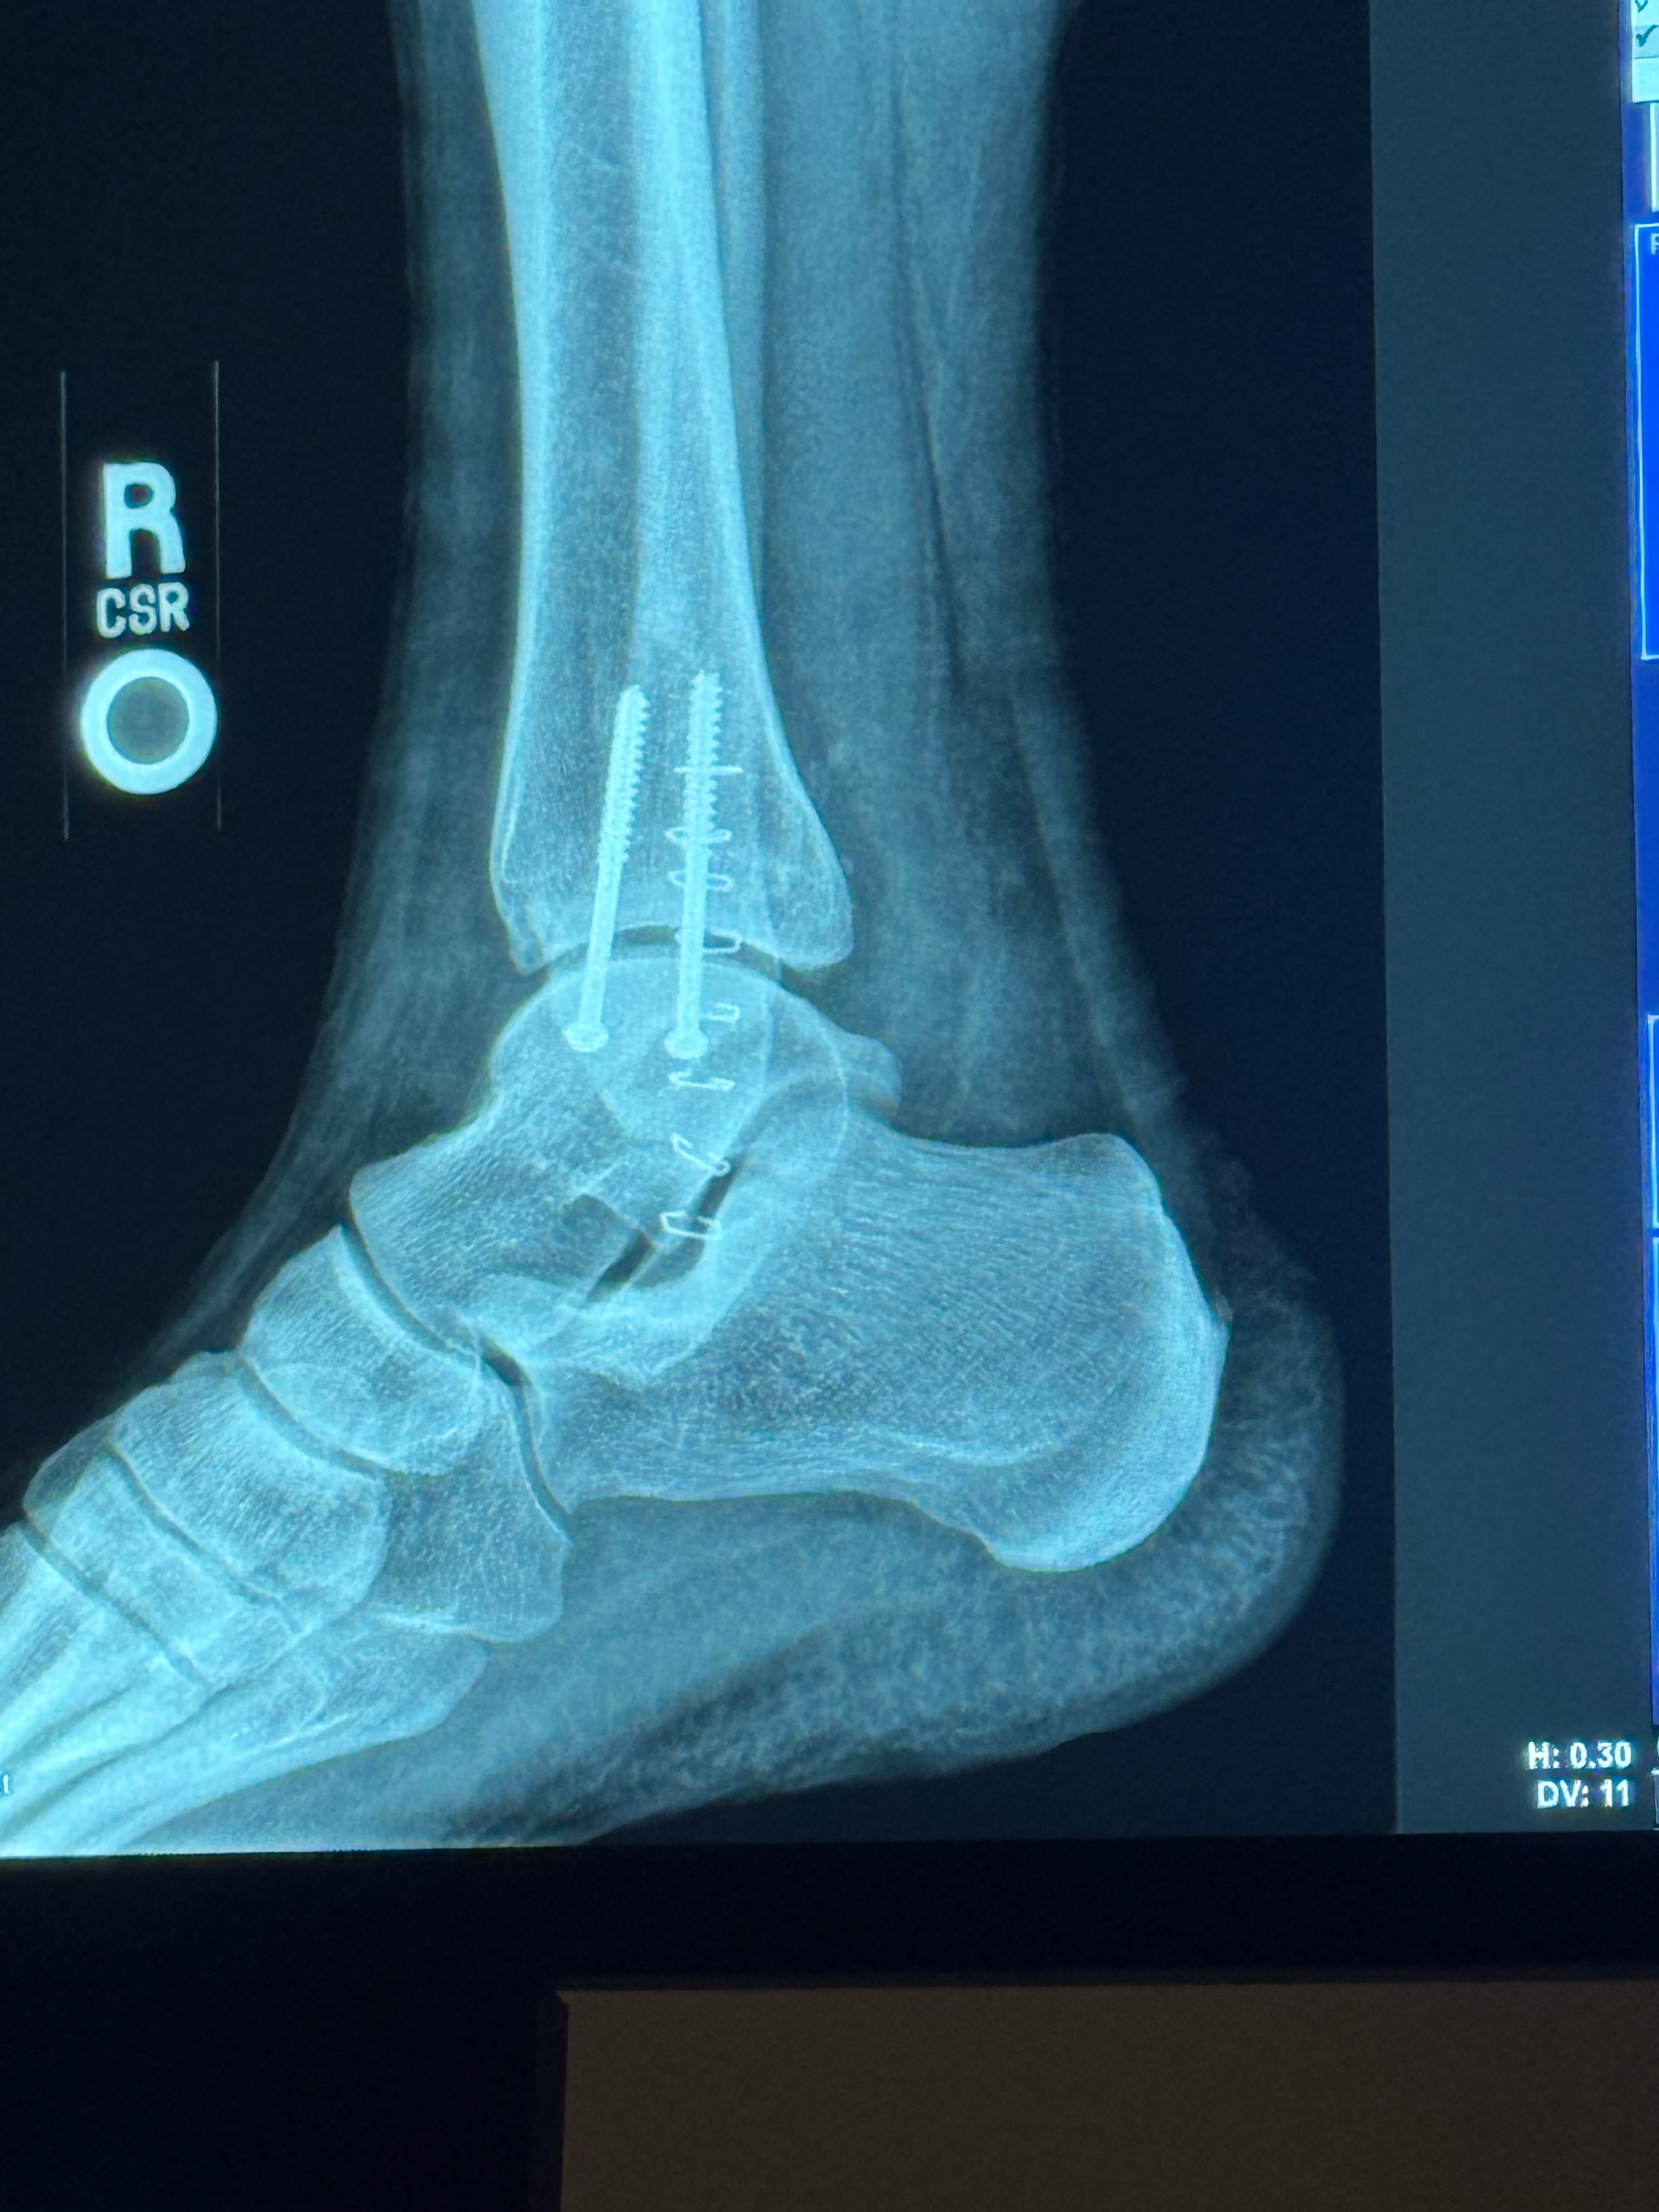

My name is Ray. I am a OIF & OIF2 veteranI who drove many miles on IED and ambush filled roads in Iraq back in 2004/5. Pity is not something I ask for and honestly, I'm very nauseous about even doing this, However, if it wasn't for my amazing wife and two amazing daughters, and the fact that I don't have a choice. That and our life is completely falling apart due to mother nature making things piling up. I can't seem to get a break on top of that, I am a 70% disabled veteran and still can't get help from the VA so Due to a deer taking me out on my motorcycle leaving me with a broken left tibia about an inch under the knee a severely dislocated broken ankle on the right leg with two screws in it I am no longer able to work at the moment. I'm going to lose my home my business but I know I won't lose my family because God is first and foremost, I am a truck driver by Trade actually an owner operator. My motorcycle insurance didn't even offer any kind of coverage to cover personal/professional expenses. i'm truly trying to keep my faith, but it's being whittled that more and more every day. I want you to know if you've read this far I am not looking for a handout but a hand up just a way to get on my feet if you have read this even the first two words, I pray God blesses you with abundance. I pray that he keeps you in his hand and never let anything happen to you and I pray these mighty things in the Lord and Savior son Jesus Christ name amen.